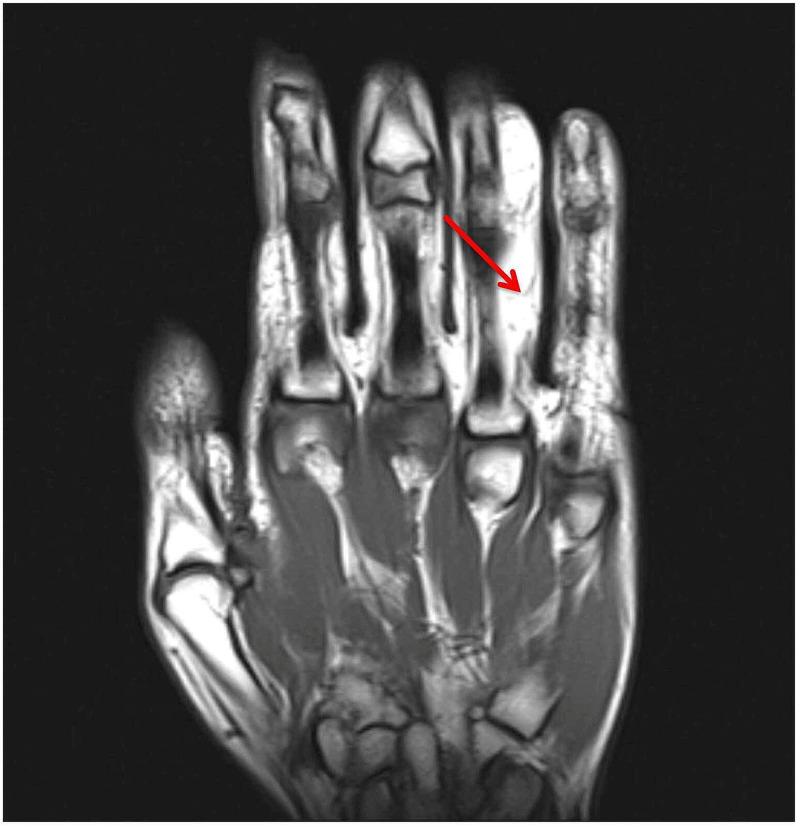

Intraneural lipomas are rare soft-tissue tumors that can occur particularly within the median nerve. Even fewer cases have been reported of their occurrence within the ulnar nerve. These masses can cause compression neuropathies. In this report, we present the first documented case of an intraneural lipoma of an ulnar digital nerve.

神经内脂肪瘤是一种罕见的软组织肿瘤,尤其可发生于正中神经内。而发生于尺神经内的病例报道则更少。这些肿物可导致压迫性神经病变。在本报告中,我们呈现了首例有记录的尺侧指神经神经内脂肪瘤病例。